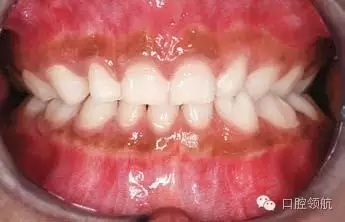

圖2.9中明顯的牙列異常有哪些?

雙側(cè)下頜側(cè)切牙和尖牙移位。

圖2.9

這種異常如何分級?

牙移位根據(jù)發(fā)生部位、牙齒類型和位置分級。這種雙側(cè)的移位分級為Mn.C.I2.